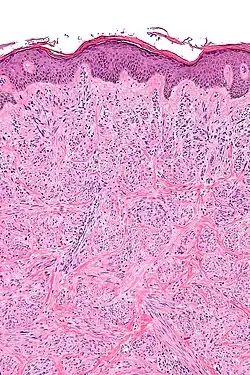

Histopatologia

Mięśniakomięsak gładkokomórkowy występuje przede wszystkim w obrębie kończyny dolnej, choć faktycznie może występować w każdej lokalizacji. Kolejnym typem klinicznym jest lokalizacja w obrębie dużych naczyń krwionośnych, głównie żyły głównej dolnej. Występowanie w naczyniach tętniczych jest rzadkie. Czwartą grupą jest lokalizacja w obrębie skóry właściwej[4]. Makroskopowo guz tworzy mięsistą, cielistą masę koloru szarego do białego lub jasnobrązowego. W pewnym stopniu zmiany mogą mieć pozawijany wygląd przypominający mięśniaka gładkokomórkowego[12][13]. Guz zwykle jest dobrze odgraniczony, choć może naciekać sąsiednie narządy, szczególnie w przypadku mięsaka w przestrzeni zaotrzewnowej. W większych guzach może być obecna martwica, ogniska krwotoczne i zmiany torbielowate[12]. Mikroskopowo mięśniakomięsak gładkokomórkowy jest utworzony przez ostro odgraniczone grupy komórek o wrzecionowatym kształcie[12]. Komórki zwykle są ułożone w pęczki, w dobrze zróżnicowanych guzach podłużne i poprzeczne pęczki mogą krzyżować się niemal pod kątem prostym. Jednak w licznych miejscach wzór nie jest tak dobrze uporządkowany i przeplatany wzór nowotworu może przypominać włókniakomięsak typu dorosłych[13]. Komórki są wydłużonego, wrzecionowatego kształtu, zawierają obfitą ilość cytoplazmy, jądro komórkowe jest charakterystycznie wydłużone. Jądra komórkowe mogą wykazać hiperchromazję i pleomorfizm. Zwykle są obecne figury mitotyczne. Cytoplazma może być eozynofilna do bladej[12].